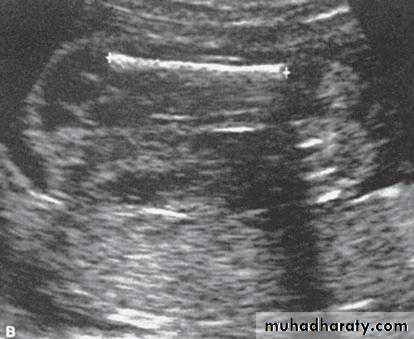

In dichorionic twin there is thick inter-twin separating membrane.

In contrast to a monochorionic twin have very thin inter-twin septum

other method is by visualizing a tongue of placental tissue within the base of dichorionic membrane which is termed the twin peak or lambda sign.